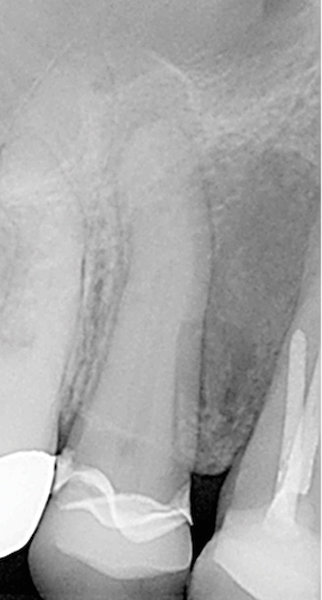

Figure 4. AND Figure 5. Before and after radiographs of bioceramic sealer hydraulically moved with the gutta-percha point. Note that the cold hydraulic technique results in lateral canal “puffs” similar to the warm vertical technique. Courtesy of Dr. Mohammed A. Alharbi.

Figure 4

Figure 5